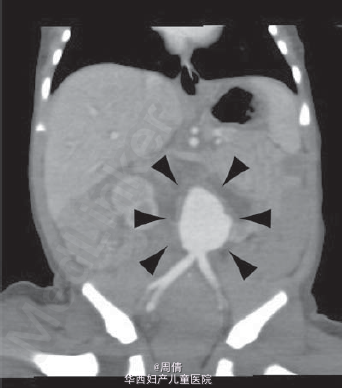

1,2.超声提示在大动脉分叉点以上的降主动脉上有一个动脉瘤,最大直径2cm 3,可见扩大的左脑室和变薄的左侧大脑实质 4,30周时胎儿MRI提示颅腔内的左侧脑室有一个增大的囊性结构

诊断为先天性腹主动脉瘤合并脑穿孔 继续妊娠,孕40周时孕妇产下一个2770g的男婴 体检提示婴儿腹部有一直径2cm的肿块 腹部CT提示降主动脉处有一直径2cm的动脉瘤 脑部CT提示左侧脑室有一囊性结构 出生第三天,MR血管造影提示胎儿期的左颈内动脉阻塞 婴儿6个月时复查腹部CT,提示降主动脉动脉瘤无明显增大,左肾动脉狭窄 因为移植如此小的血管困难太大,所以并未进行手术治疗 但是使用了VP分流器来阻止脑积水的进展